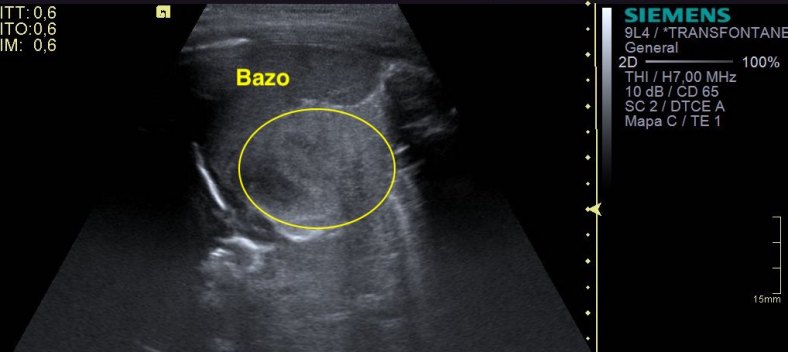

Al llegar al lado izquierdo de la paciente nos encontramos con esta imagen que vas a ver a continuación…

En la imagen 3 ves el bazo en un corte longitudinal, sin embargo en el área que marca la linea circular amarilla, se objetiva un aumento que no es normal, al seguir descendiendo, nos encontramos con la imagen 4 y la 5 donde puedes observar una lesión heterogénea, de casi 5 cms que ocupa la teórica posición anatómica de la suprarrenal izquierda.

Por tanto y situado en flanco izquierdo tenemos una colección de contornos bien definidos, de aspecto heterogéneo, anecoica, con focos de mayor ecogenicidad, de 46 x 28 x 34 mm, en teórica localización de la glándula suprarrenal, hallazgos sugerentes de hemorragia suprarrenal.